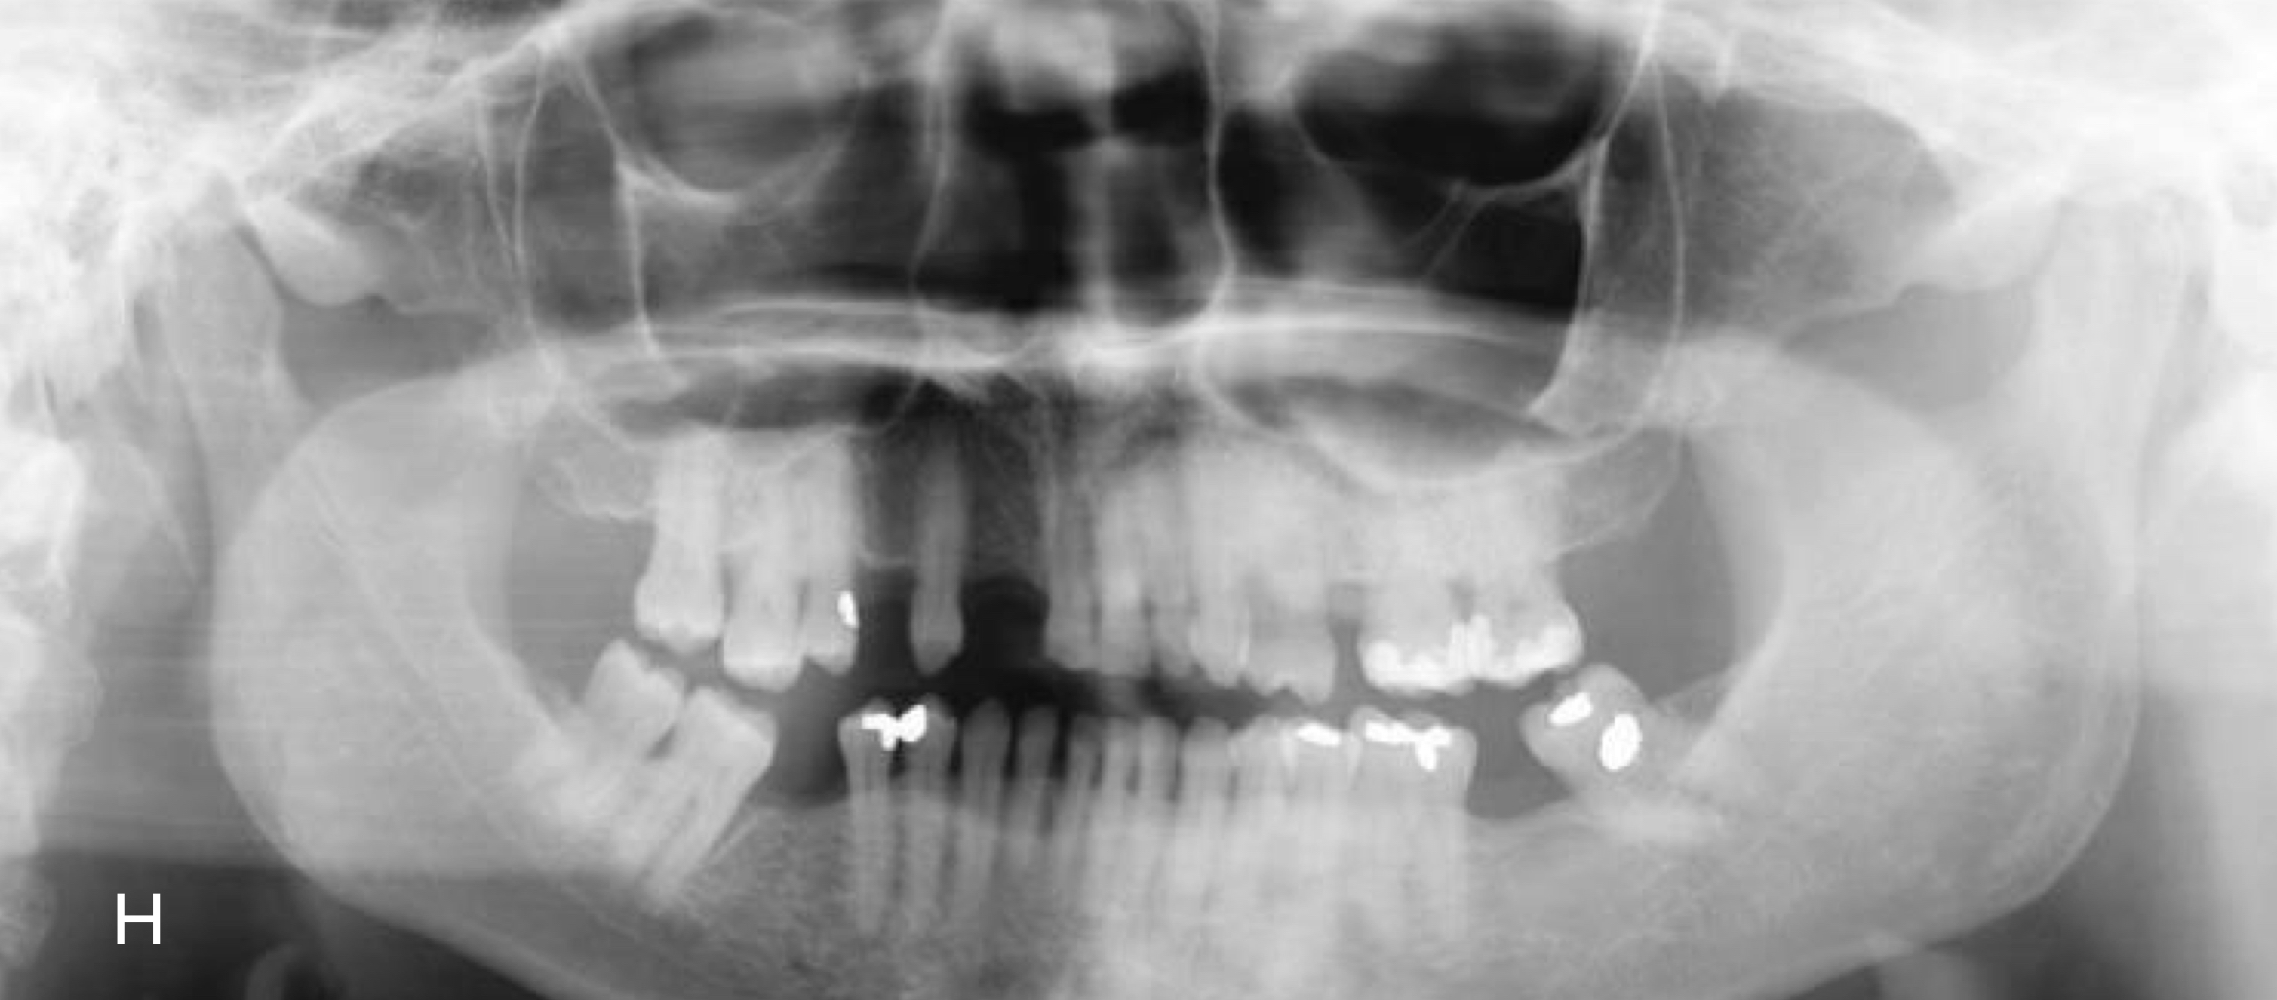

Why would we use a panoramic image?

To see dentition, joints, cysts, trauma, can't get intraoral images

What are disadvantages of panoramic images?

Magnification of image, low resolution, ghost images, positioning errors, difficult to decipher

What happens when the mandible is at the center of the focal trough?

Minimal distortion of image

What happens if the mandible is posterior to focal trough?

Widening of image